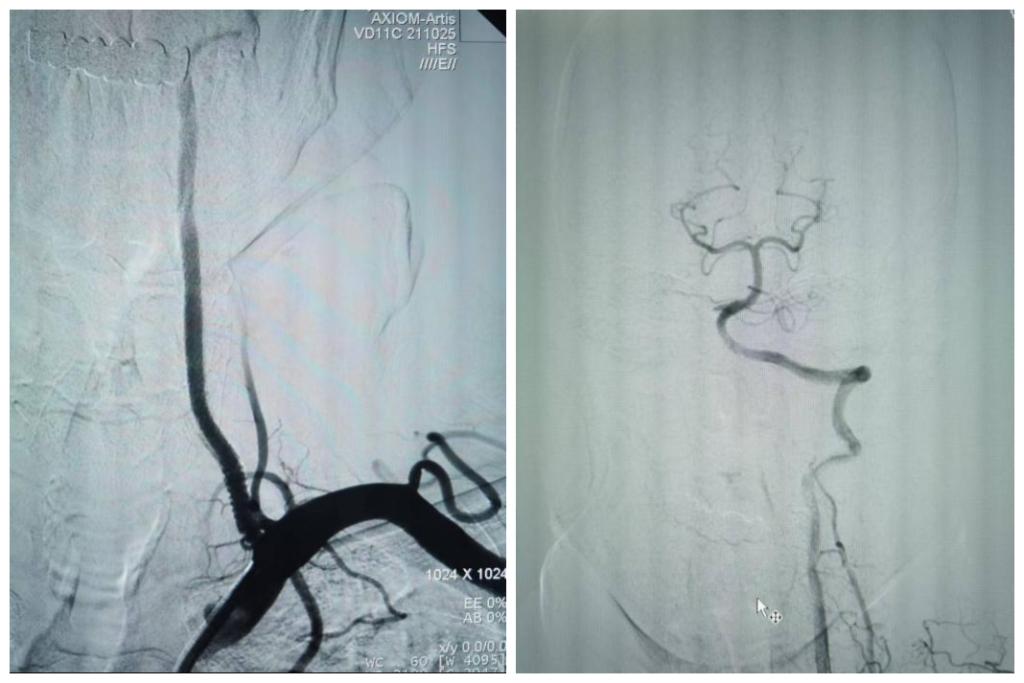

患者拜某,男,65岁,因反复头晕、晕厥1年,加重10天入院,既往5年前因心肌梗死在外院冠脉植入5枚支架。本次发病后当地医院发现患者脑后部的主干动脉——双侧椎动脉在颈部完全闭塞,当地医院药物医治无效,患者慕名从商洛来到我院神经内科。入院后经过脑血管造影发现患者双侧椎动脉颈部闭塞段大约10cm,闭塞远端经过甲状颈干及肋颈干向V2近颅底以远代偿供血,但因代偿不足,患者近来反复脑梗死2次,此次入院再次提示小脑新鲜脑梗死。

最终,在患者入院第4天,张桂莲教授带领的介入团队选择局麻条件下为患者成功实施了神经介入领域的高难度手术—左侧无残端椎动脉长节段慢性闭塞再通术。因术前清晰的影像显影及准确的体外定位标记,左侧优势椎动脉顺利开通,手术耗时仅仅约90分钟。术中及术后患者配合良好,无任何不适,术后在介入准备室,张桂莲教授向患者女儿详细告知手术过程及患者目前状况,患者女儿喜极而泣,多次向介入团队表示感谢。

出院前复查头颈一体化超声提示左侧椎动脉支架位置良好,血流通畅,颅内血流速度及频谱未见明显异常。充分向患者及家属告知出院注意事项及复查时间后,目前该患者已顺利出院。